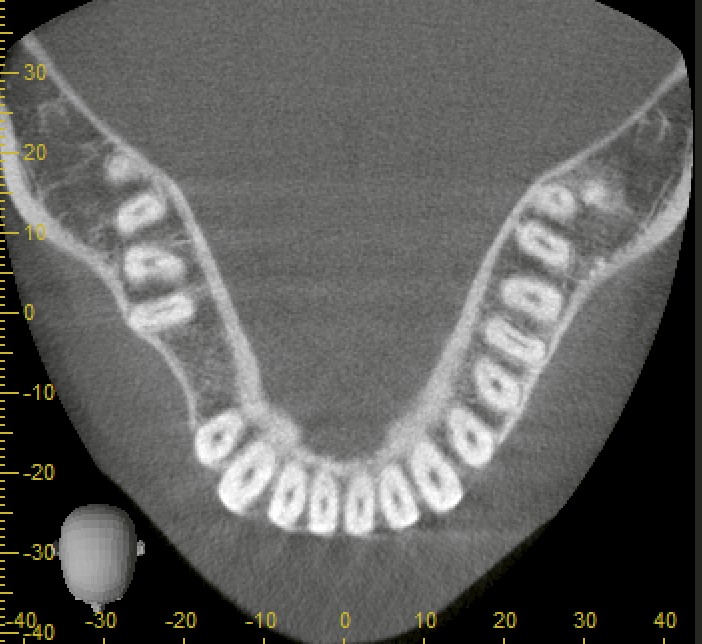

CT・パノラマレントゲンで確認すると、

* 骨幅・骨量ともに十分

* 大きな骨欠損もなし

と良好な条件でした。